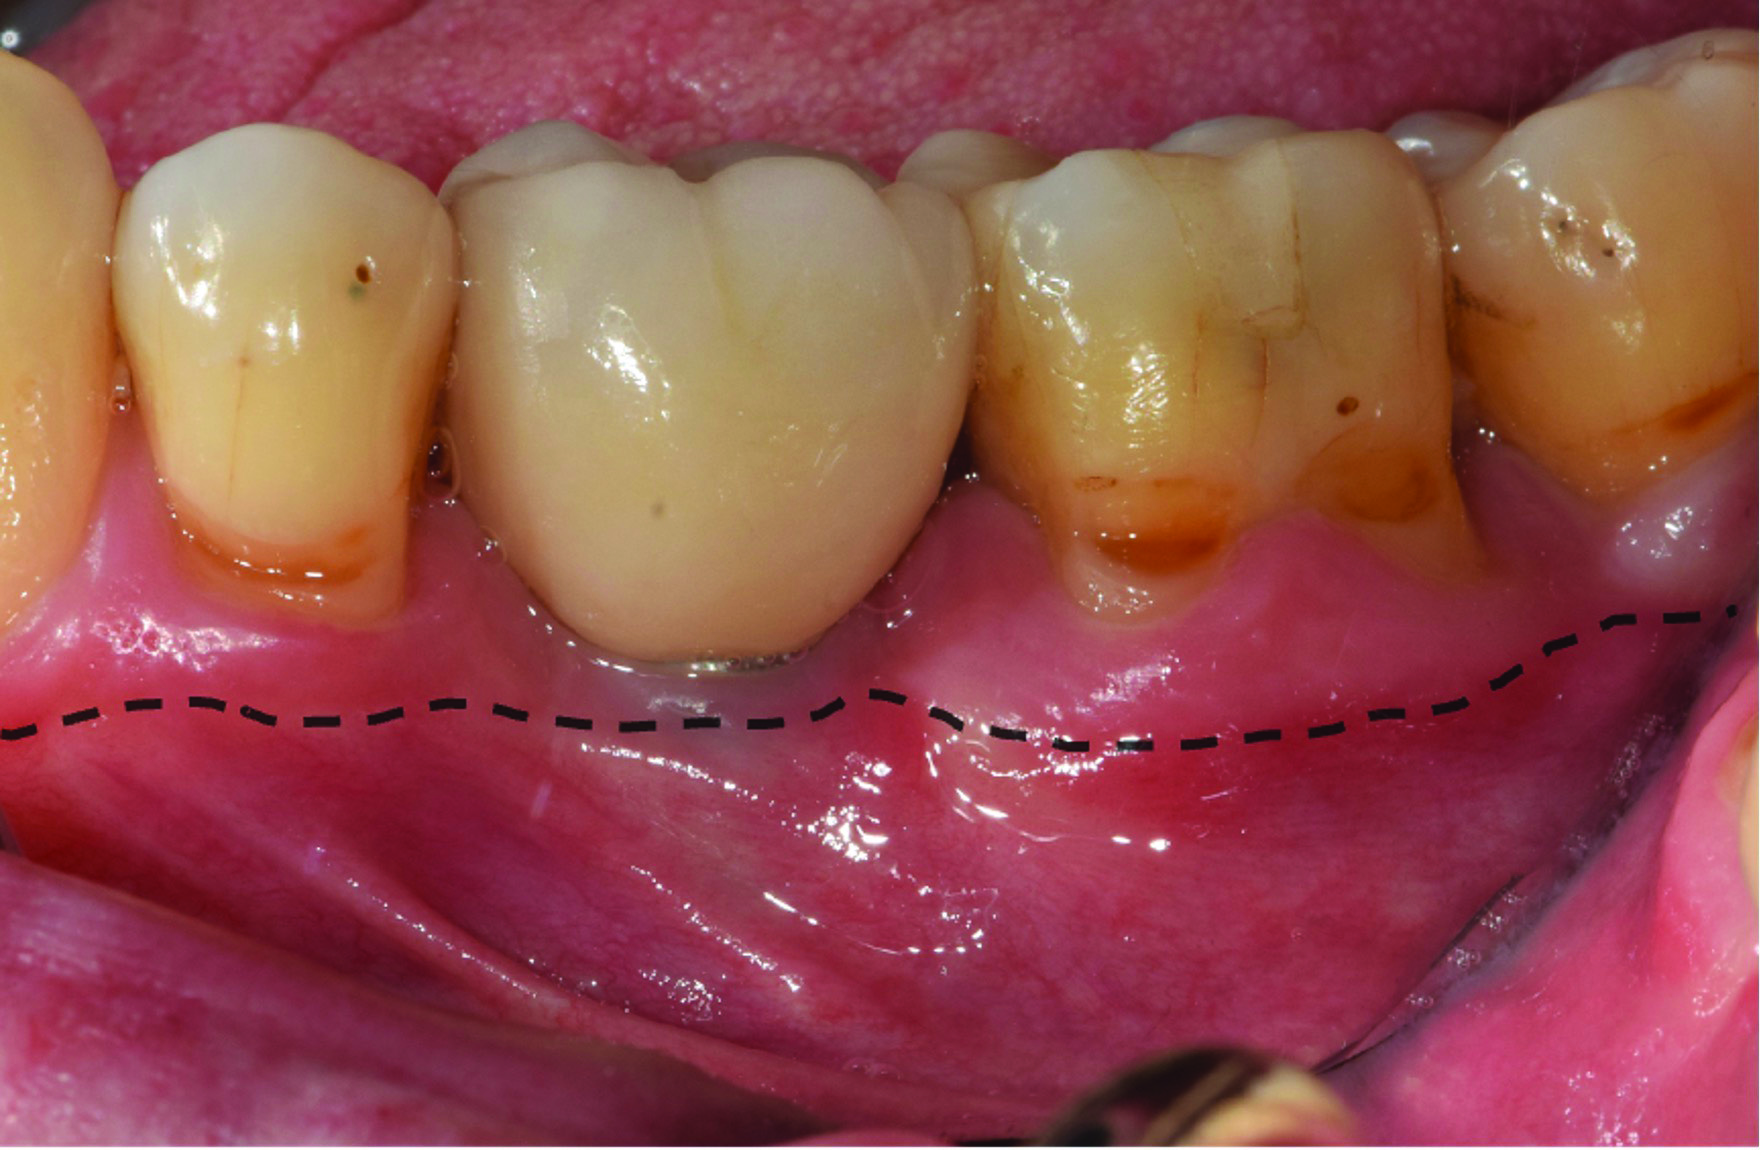

Fig 1. The peri-implant mucosa of implant No. 19 presents erythema with a lack of KMW. The dark color of the underlying restoration is showing through the thin peri-implant mucosa. The dotted line indicates the MGJ. The distance from the margin of the peri-implant mucosa to the MGJ is the KMW.

Figure 1

A deficient dimension of keratinized mucosa width (KMW) around dental implants is often related to patient discomfort during oral hygiene (Figure 1). Literature suggests the dimension of KMW should be considered as a risk factor for peri-implant mucositis and peri-implantitis.1-4 KMW is also associated with patient satisfaction regarding implant esthetics. Mucosal thickness (MT) is crucial for both esthetic outcomes and peri-implant health.5-7 Thicker mucosal tissue provides stability for the mucosal margin, which leads to less risk of mucosal recession. This underscores the importance of considering tissue thickness in implant planning and restoration.

KMW is the dimension of keratinized soft tissue extending from the mucosal margin to the mucogingival junction (MGJ) in the apicocoronal direction. KMW is the coronal component of the peri-implant soft tissues, and beyond these tissues apically is the non-keratinized alveolar mucosa (Figure 1 through Figure 3). Where KMW is absent in certain conditions, there is solely non-keratinized peri-implant mucosa adaptation to the implant prosthesis. KMW is measured clinically with an instrument such as a periodontal probe in the apicocoronal direction, or an estimate of KMW can be made based on photographs. While as a clinical guideline or for research purposes it has been proposed that at least 2 mm of KMW be present, this amount is still debated as to whether or not it is necessary.8

MT is the horizontal dimension of the peri-implant soft tissue and may or may not be keratinized. MT is an important aspect of implant esthetic outcomes, especially at the most coronal aspect around the implant restoration. Around thin mucosa the color of the underlying restoration material may show through and result in esthetic deficiencies (Figure 1). Conversely, thick tissue can minimize the shading effect of underlying restoration materials and may compensate for any bony dehiscence around the implant body. In a systematic review, it was reported that after soft-tissue augmentation was conducted to increase MT, less interproximal marginal bone loss resulted around the implant.9